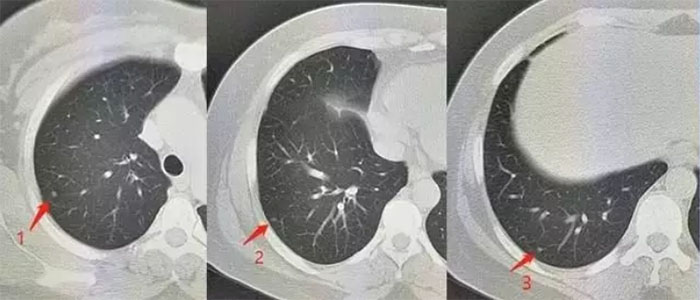

众所周知,肺癌的可怕之处就是出现临床症状时(如胸闷、刺激性干咳、咳血等),往往预示着肺癌已不是早期,这就需要“胸部CT”与“肺结节自身抗体检测”的结合,从影像学及分子生物学两方面,更加准确的对病灶进行综合评估与定性,从而达到“早发现、早诊断、早治疗”的目的。经各研究和随访的数据统计,肺结节自身抗体检测阳性率预测值可达88%。

① 结果为【CT(+),抗体(+)】,需临床干预。

②结果为【CT(-),抗体(+)】或【CT(+),抗体(-)】,需定期复查CT。

③ 结果为【CT(-),抗体(-)】,肺部健康。